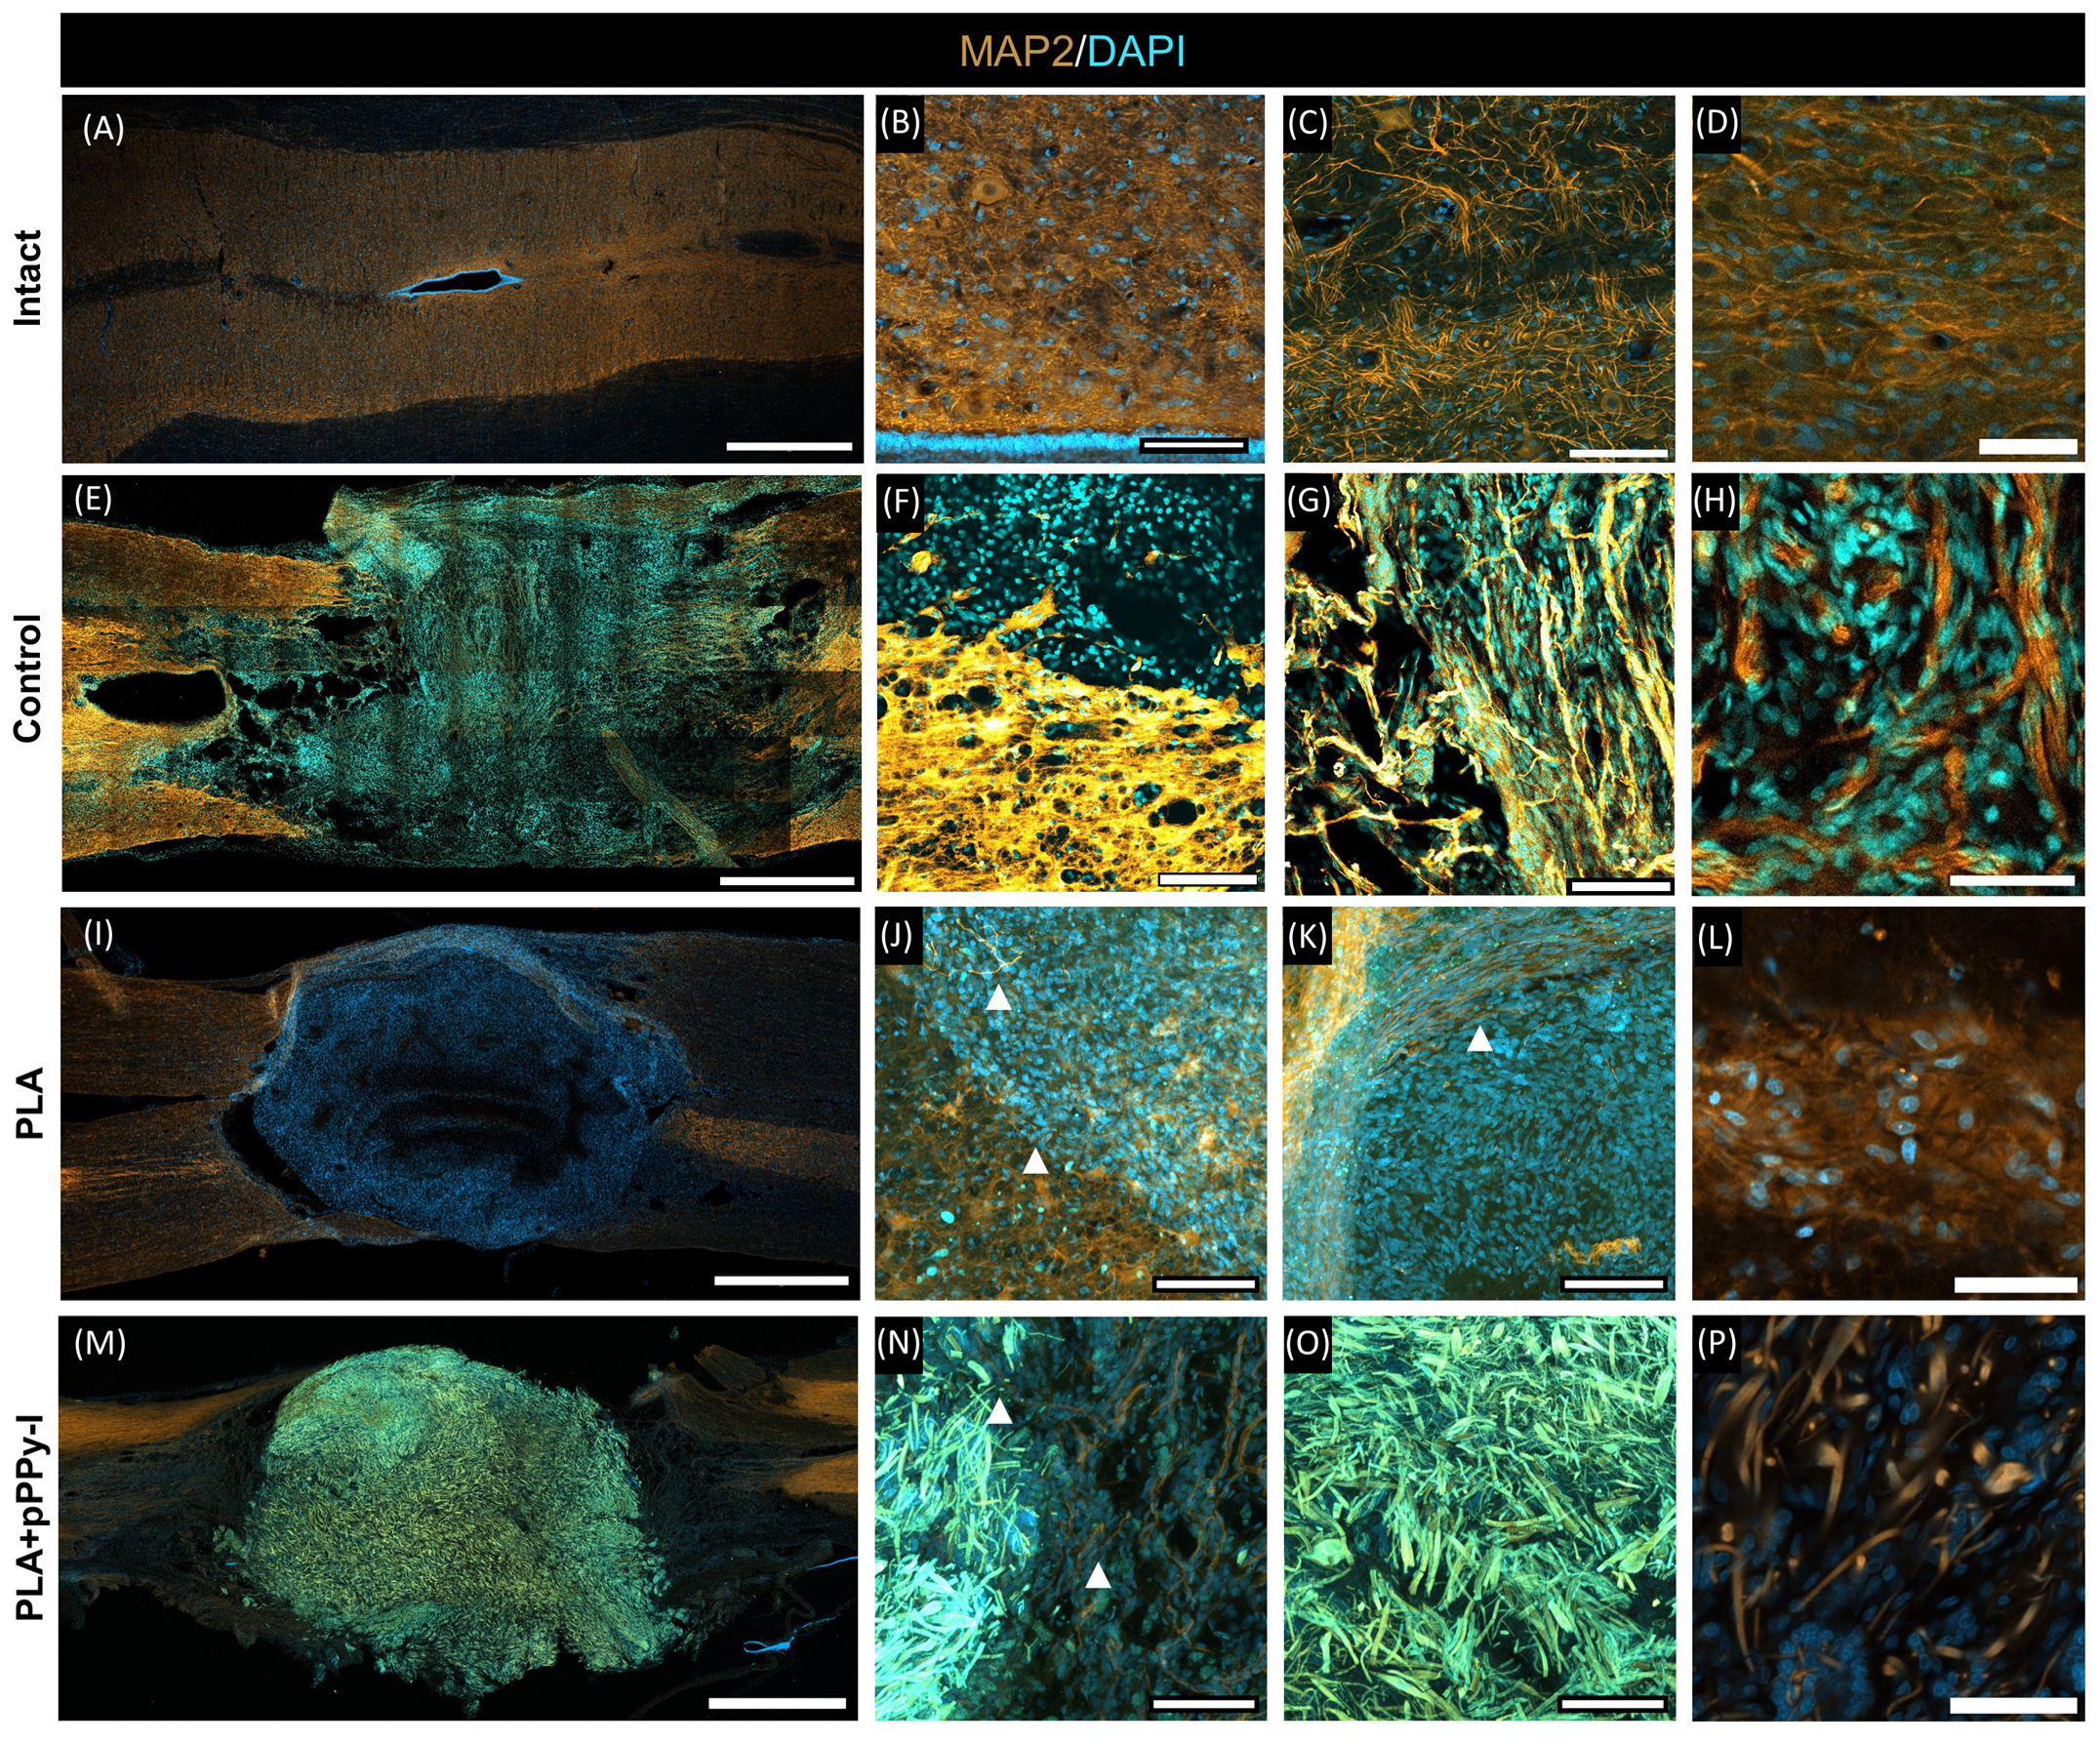

3.8. Evidence of Neuronal Marker MAP2 over the Fibers Demonstrated Fibrillar Scaffolds Are Potential Substrates for Nerve Repair